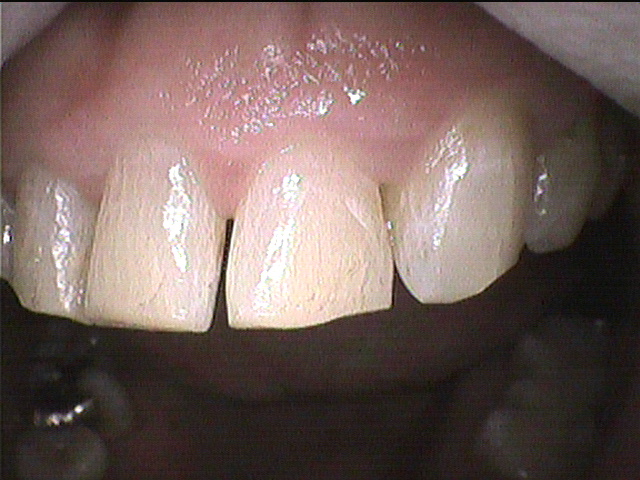

◎クリーニング後

綺麗になりました✨

着色汚れ(ステイン)は歯ブラシで磨いてもなかなか落ちません😥

歯科医院専用の機械で磨いて落としました。